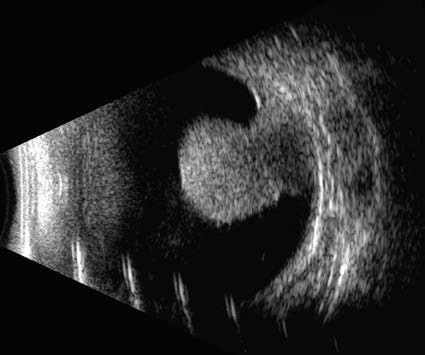

Figure 1 B-scan ultrasound imaging of choroidal melanoma in the right eye

A mushroom-shaped elevated lesion is observed in the posterior segment of the right eye, measuring 11.8 mm × 10.8 mm × 10.0 mm. The lesion exhibits medium-to-low internal echogenicity, accompanied by a "choroidal excavation sign" and surrounding areas of strong, band-like echoes, consistent with choroidal melanoma with retinal detachment.